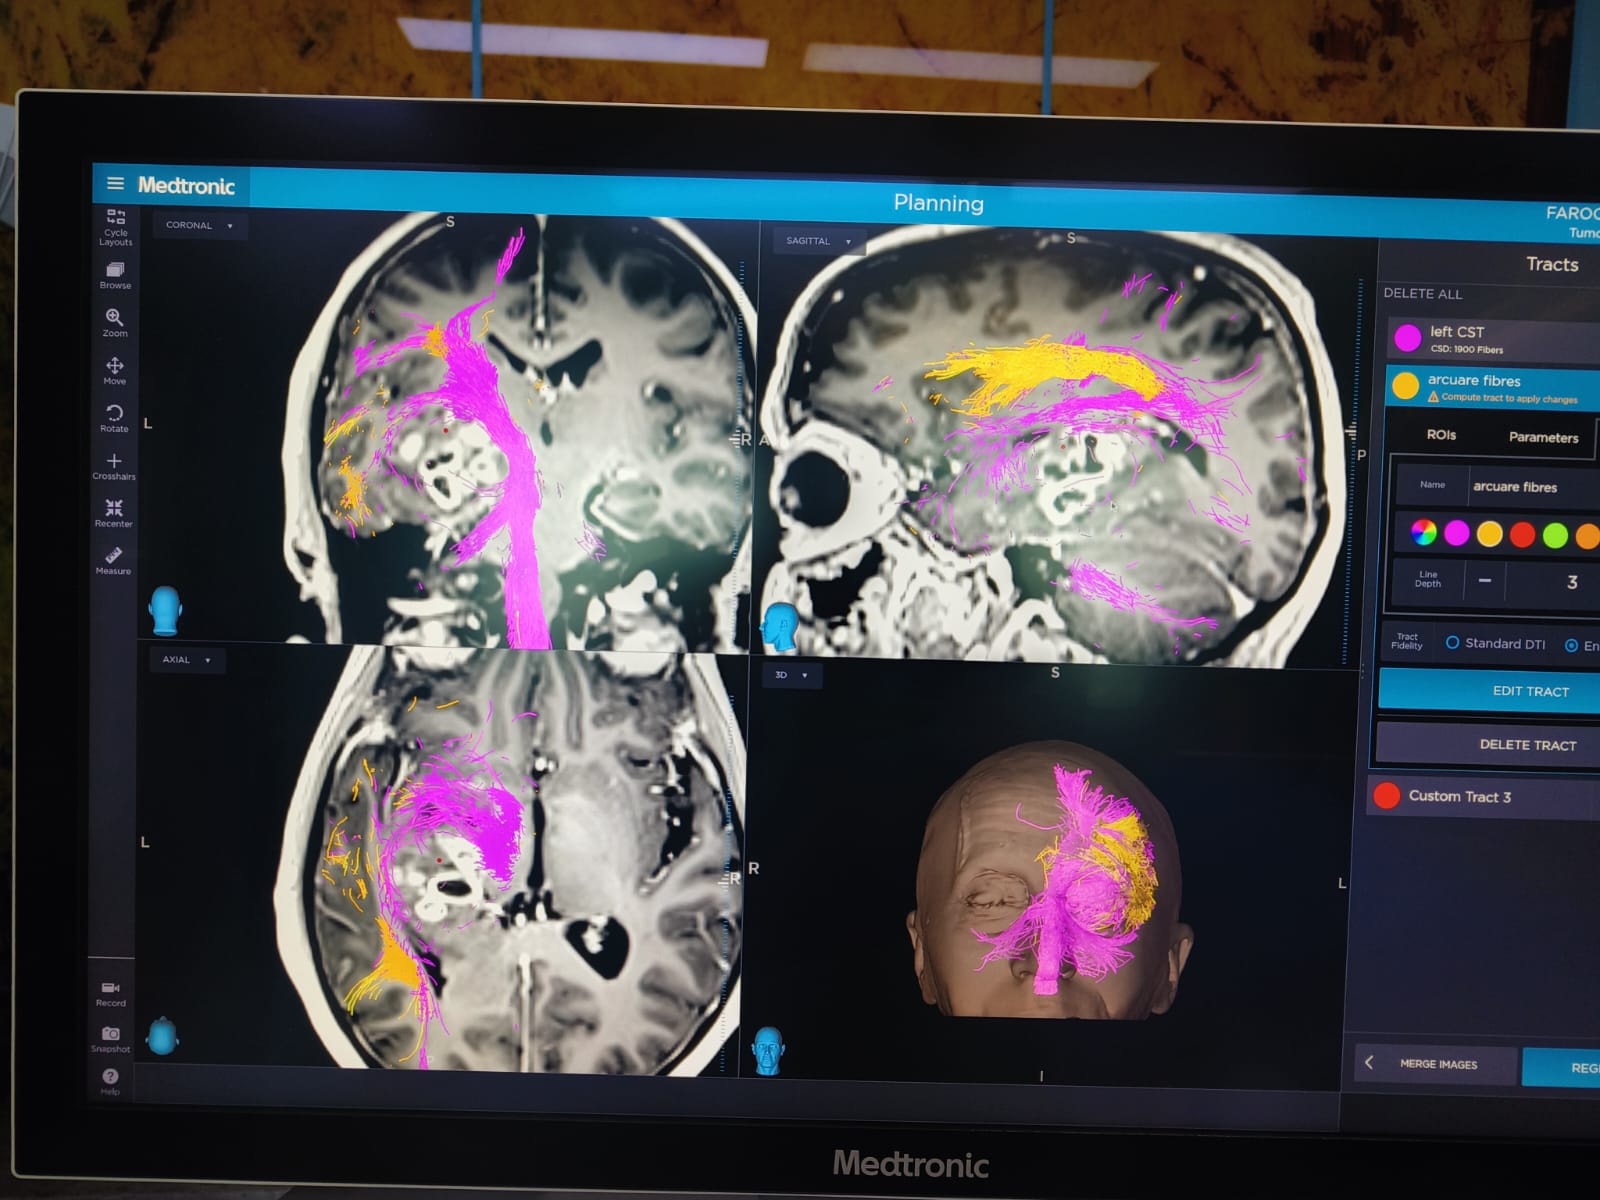

Brain Tumor Surgery